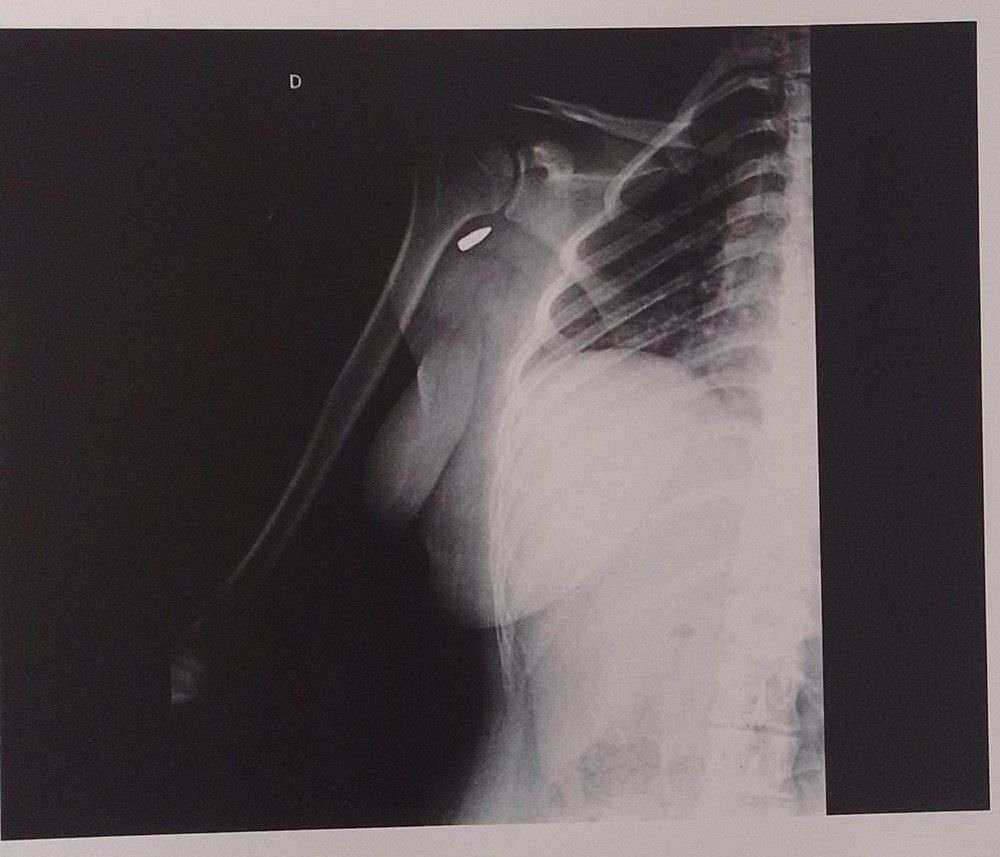

Renata começou a sentir muito dor e contou para os amigos que achava que tinha tomado um tiro mas eles não estavam acreditando. Ao chegar em casa na madrugada de domingo (20), ela contou para mãe o que tinha acontecido. As duas foram a uma emergência e viram – em um exame de imagem – que a bala estava alojada no braço direito.

A estudante continua com a bala alojada no ombro porque, segundo ela, os médicos informaram que com a tentativa de retirar o projétil ela correria risco de perder os movimentos do braço. O caso aconteceu em um pagode em Rocha Miranda, na zona norte do Rio de Janeiro.